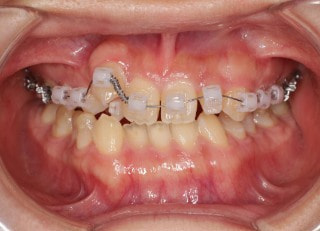

治療法:フルパッシブブラケット:T21

解説:下顎前突上顎劣勢長傾向で、上顎両側2番が矮小歯、右下2番先天欠如症例なので、上下前歯の幅径の比率を調節する必要があるケースです。(ご本人のご都合で治療中に来院できない期間がありました)

治療開始時